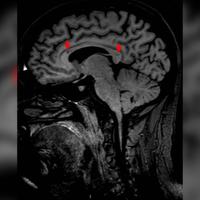

77岁老年男性,突发昏迷24小时入院。既

77岁老年男性,突发昏迷24小时入院。既往无高血压病史。近半年右前臂背侧常有皮下淤血斑。...

由 medjpg 发表于 2026-03-24 22:32